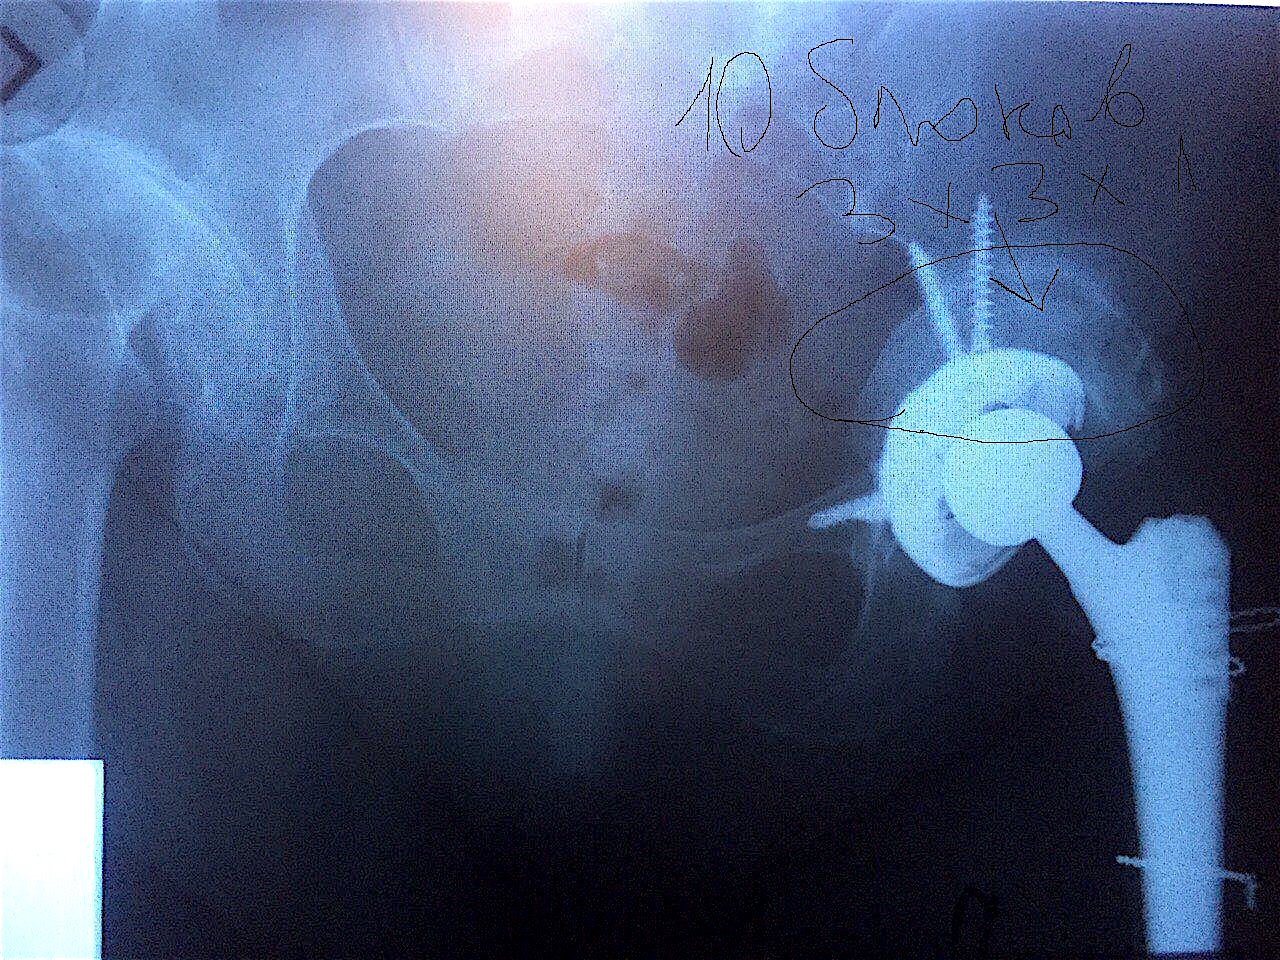

Сделано тотальное эндопротезирование левого тазобедренного сустава с компенсацией дефицита вертлужной впадины костным аллотрансплантатом «Лиопласт» (в количестве 10 шт. губчатых блоков 3х3х1 см).